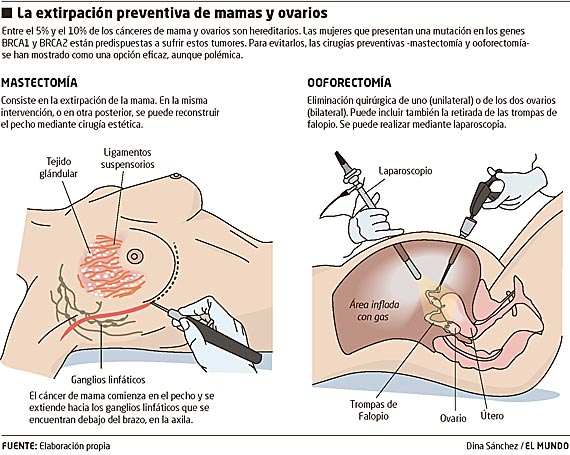

HISTERECTOMÍA.

Operación para extirpar el útero a través de una incisión en el abdomen o a través de la vagina. Se puede realizar la extirpación de los ovarios al mismo tiempo.

OOFORECTOMÍA:

Es la extirpación de un ovario. Puede ser unilateral, cuando se extirpa únicamente uno de los dos ovarios, o bilateral cuando ambos ovarios son extirpados

TROMPAS DE FALOPIO

Son conductos musculares que conectan los ovarios y el útero o matriz. Sus funciones están relacionadas con la ovulación, con lafecundación y con el embarazo